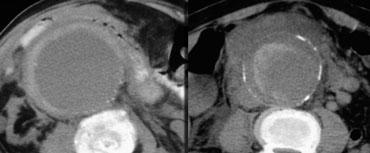

Gián đoạn khu trú của vôi hóa lớp nội mạc

Một dấu hiệu khác của vỡ phình sắp xảy ra hoặc rò rỉ khu trú là sự gián đoạn khu trú của vôi hóa lớp nội mạc.

Trong hầu hết các trường hợp này, chúng ta cũng có thể nhận thấy dấu hiệu canxi tiếp tuyến.

Trong những trường hợp này, hình ảnh cho thấy vôi hóa như đang chỉ ra ngoài chu vi dự kiến của túi phình.

Dấu hiệu canxi tiếp tuyến

Bên trái là một ví dụ khác về dấu hiệu canxi tiếp tuyến.

Vôi hóa lớp nội mạc hướng ra ngoài túi phình và có rò rỉ sau phúc mạc.